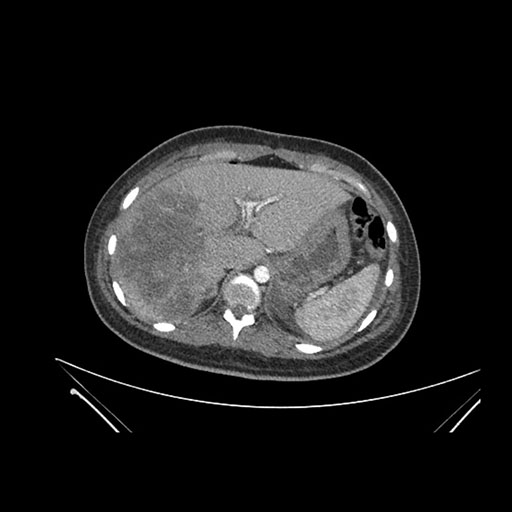

Axial Venous